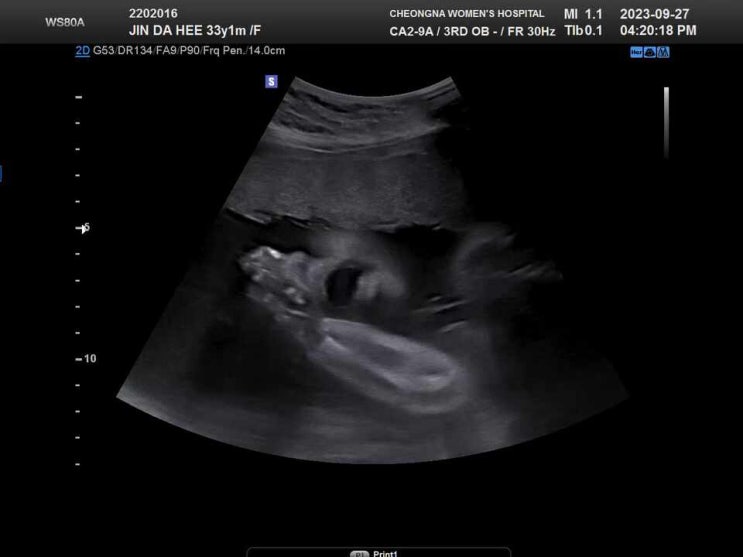

[임신일기 다섯번째] 32주차 셀프 만삭사진촬영 부천 베러픽스튜디오, 33주차 태동검사

[임신일기 네번째] 임신 29주차 정기검진

임신 29주차! 저번에 임당 재검때문에 한 2주만에 방문하는 것 같은 정기검진ㅎㅎ 추석 전날이라 회사가 점...

[임신일기 세번째] 임산부 27주차,28주차 임신성 당뇨 검사, 재검확정 후 재검 통과 후기 그리고, 정밀초음파로 우리아기 얼굴 베이비페이스 예측하기

임신 27주차에 임신 당뇨 검사가 있는데요, 임신성 당뇨 검사란, 임신에 따른 호르몬과 물질 대사의 변화로...